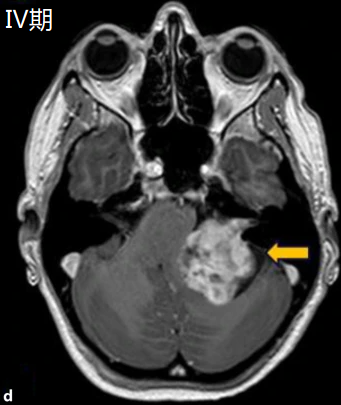

- Ⅳ期:脑干及脑室受压期

大型或巨大型肿瘤,肿瘤直径>30mm。使脑干明显移位,脑干受损明显,产生行走不稳和头痛等症状,压迫严重时可能出现言语障碍和吞咽困难,甚至产生意识障碍,如淡漠、嗜睡、痴呆甚至昏迷。